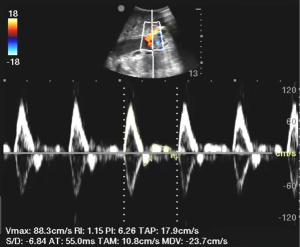

For RRI measurement (11), intrarenal vessels were located on the coronal plane of the kidney. Blood flow velocity was measured for two to three arteries of each kidney, with three continuous velocity waveforms obtained for each artery. The median value was taken as the resistance index of each artery, and the median resistance index of multiple arteries was considered the resistance index of each kidney (Figure 2).